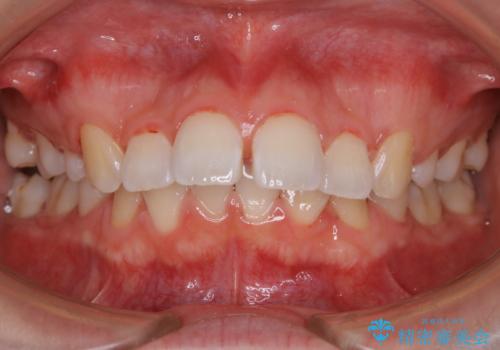

ワイヤー矯正中のクリーニング

担当医 歯科衛生士